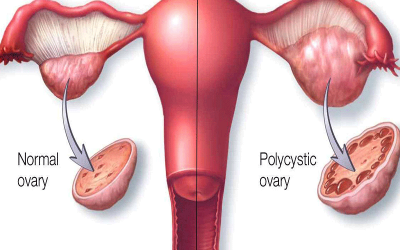

کیست های خطرناک تخمدان

کیست تخمدان یک بیماری شایع است که در صورت عدم درمان می تواند مشکلاتی را برای بیمار به همراه داشته باشد ، از این رو توصیه می...